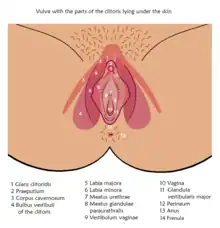

In mammals, the vulva (pl.: vulvas or vulvae) consists of the external female genitalia. The human vulva includes the mons pubis (or mons veneris), labia majora, labia minora, clitoris, vestibular bulbs, vulval vestibule, urinary meatus, the vaginal opening, hymen, and Bartholin's and Skene's vestibular glands. The urinary meatus is also included as it opens into the vulval vestibule. Other features of the vulva include the pudendal cleft, sebaceous glands, the urogenital triangle (anterior part of the perineum), and pubic hair. The vulva includes the entrance to the vagina, which leads to the uterus, and provides a double layer of protection for this by the folds of the outer and inner labia. Pelvic floor muscles support the structures of the vulva. Other muscles of the urogenital triangle also give support.

Structure

The main structures of the vulva are: the mons pubis, the labia – labia majora and labia minora, the external parts of the clitoris – the clitoral hood and the glans, the urinary meatus, the vaginal opening and hymen, and Bartholin's and Skene's vestibular glands.[1] Other features include the pudendal cleft, pubic hair, sebaceous glands, the vulval vestibule, and the urogenital triangle.[2]

The labia majora and the labia minora cover the vulval vestibule.[8] The outer pair of folds, divided by the pudendal cleft, are the labia majora (Neo-Latin for "larger lips"). They contain and protect the other structures of the vulva.[8] The labia majora meet at the front at the mons pubis, and meet posteriorly at the urogenital triangle (the anterior part of the perineum) between the pudendal cleft and the anus.[9][6] The labia minora are often pink or brownish black, relevant to the person's skin color.[10]

The grooves between the labia majora and labia minora are called the interlabial sulci, or interlabial folds.[11] The labia minora (smaller lips) are the inner two soft folds, within the labia majora. They have more color than the labia majora[3] and contain numerous sebaceous glands.[12] They meet posteriorly at the frenulum of the labia minora, a fold of restrictive tissue. The labia minora meet again at the front of the vulva to form the clitoral hood, also known as the prepuce.[13]

The visible portion of the clitoris is the clitoral glans. Typically, this is roughly the size and shape of a pea, and can vary in size from about 6 mm to 25 mm.[13] The size can also vary when it is erect.[6] The clitoral glans contains as many nerve endings as the much larger homologous glans penis in the male, which makes it highly sensitive.[13] The only known function of the clitoris is to focus sexual feelings.[13] The clitoral hood is a protective fold of skin which varies in shape and size, and it may partially or completely cover the clitoris.[14] The clitoris is the homologue of the penis,[8] and the clitoral hood is the female equivalent of the male foreskin,[14] and may be partially or completely hidden within the pudendal cleft.[15]

Vestibule

The area between the labia minora where the vaginal opening and the urinary meatus are located is called the vulval vestibule, or vestibule of the vagina. The urinary meatus is below the clitoris and just in front of the vaginal opening which is near to the perineum. The term introitus is more technically correct than "opening", since the vagina is usually collapsed, with the opening closed. The introitus is sometimes partly covered by a membrane called the hymen. The hymen will usually rupture during the first episode of vigorous sex, and the blood produced by this rupture has been seen to signify virginity. However, the hymen may also rupture spontaneously during exercise or be stretched by normal activities such as the use of tampons and menstrual cups, or be so minor as to be unnoticeable, or be absent.[13] In some rare cases, the hymen may completely cover the vaginal opening, requiring a surgical procedure called a hymenotomy.[16] On either side of the back part of the vaginal opening are the two greater vestibular glands known as Bartholin's glands. These glands secrete mucus and a vaginal and vulval lubricant.[17] They are homologous to the bulbourethral glands in the male.[2] The lesser vestibular glands known as Skene's glands, are found on the anterior wall of the vagina. They are homologues of the male prostate gland and are also referred to as the female prostate.[18]

Pelvic floor muscles help to support the vulvar structures. The voluntary, pubococcygeus muscle, part of the levator ani muscle partially constricts the vaginal opening.[19] Other muscles of the urogenital triangle support the vulvar area and they include the transverse perineal muscles, the bulbospongiosus, and the ischiocavernosus muscles.[20] The bulbospongiosus muscle decreases the vaginal opening.[9] Their contractions play a role in the vaginal contractions of orgasm by causing the vestibular bulbs to contract.[21]